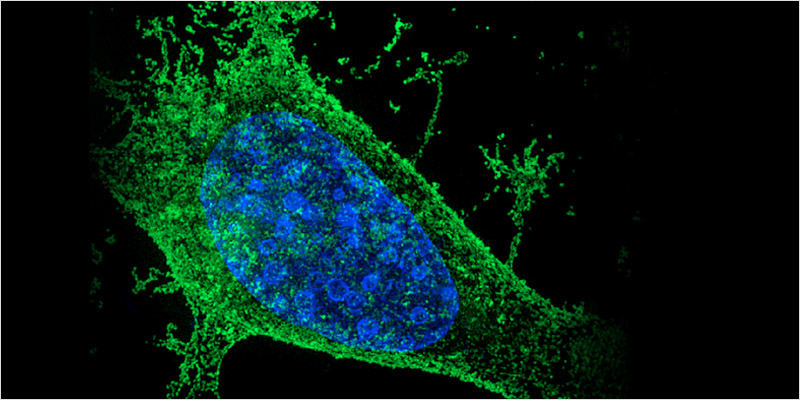

- Rak

To już w zasadzie niepodważalny fakt: konopie zabijają komórki rakowe. Od dziesięcioleci naukowcy badają wpływ konopi na różne rodzaje nowotworów. Poza łagodzeniem nudności, które są rezultatem chemioterapii, są dowody na to, że konopie zmniejszają ilość komórek rakowych.

To już w zasadzie niepodważalny fakt: konopie zabijają komórki rakowe. Od dziesięcioleci naukowcy badają wpływ konopi na różne rodzaje nowotworów. Poza łagodzeniem nudności, które są rezultatem chemioterapii, są dowody na to, że konopie zmniejszają ilość komórek rakowych.